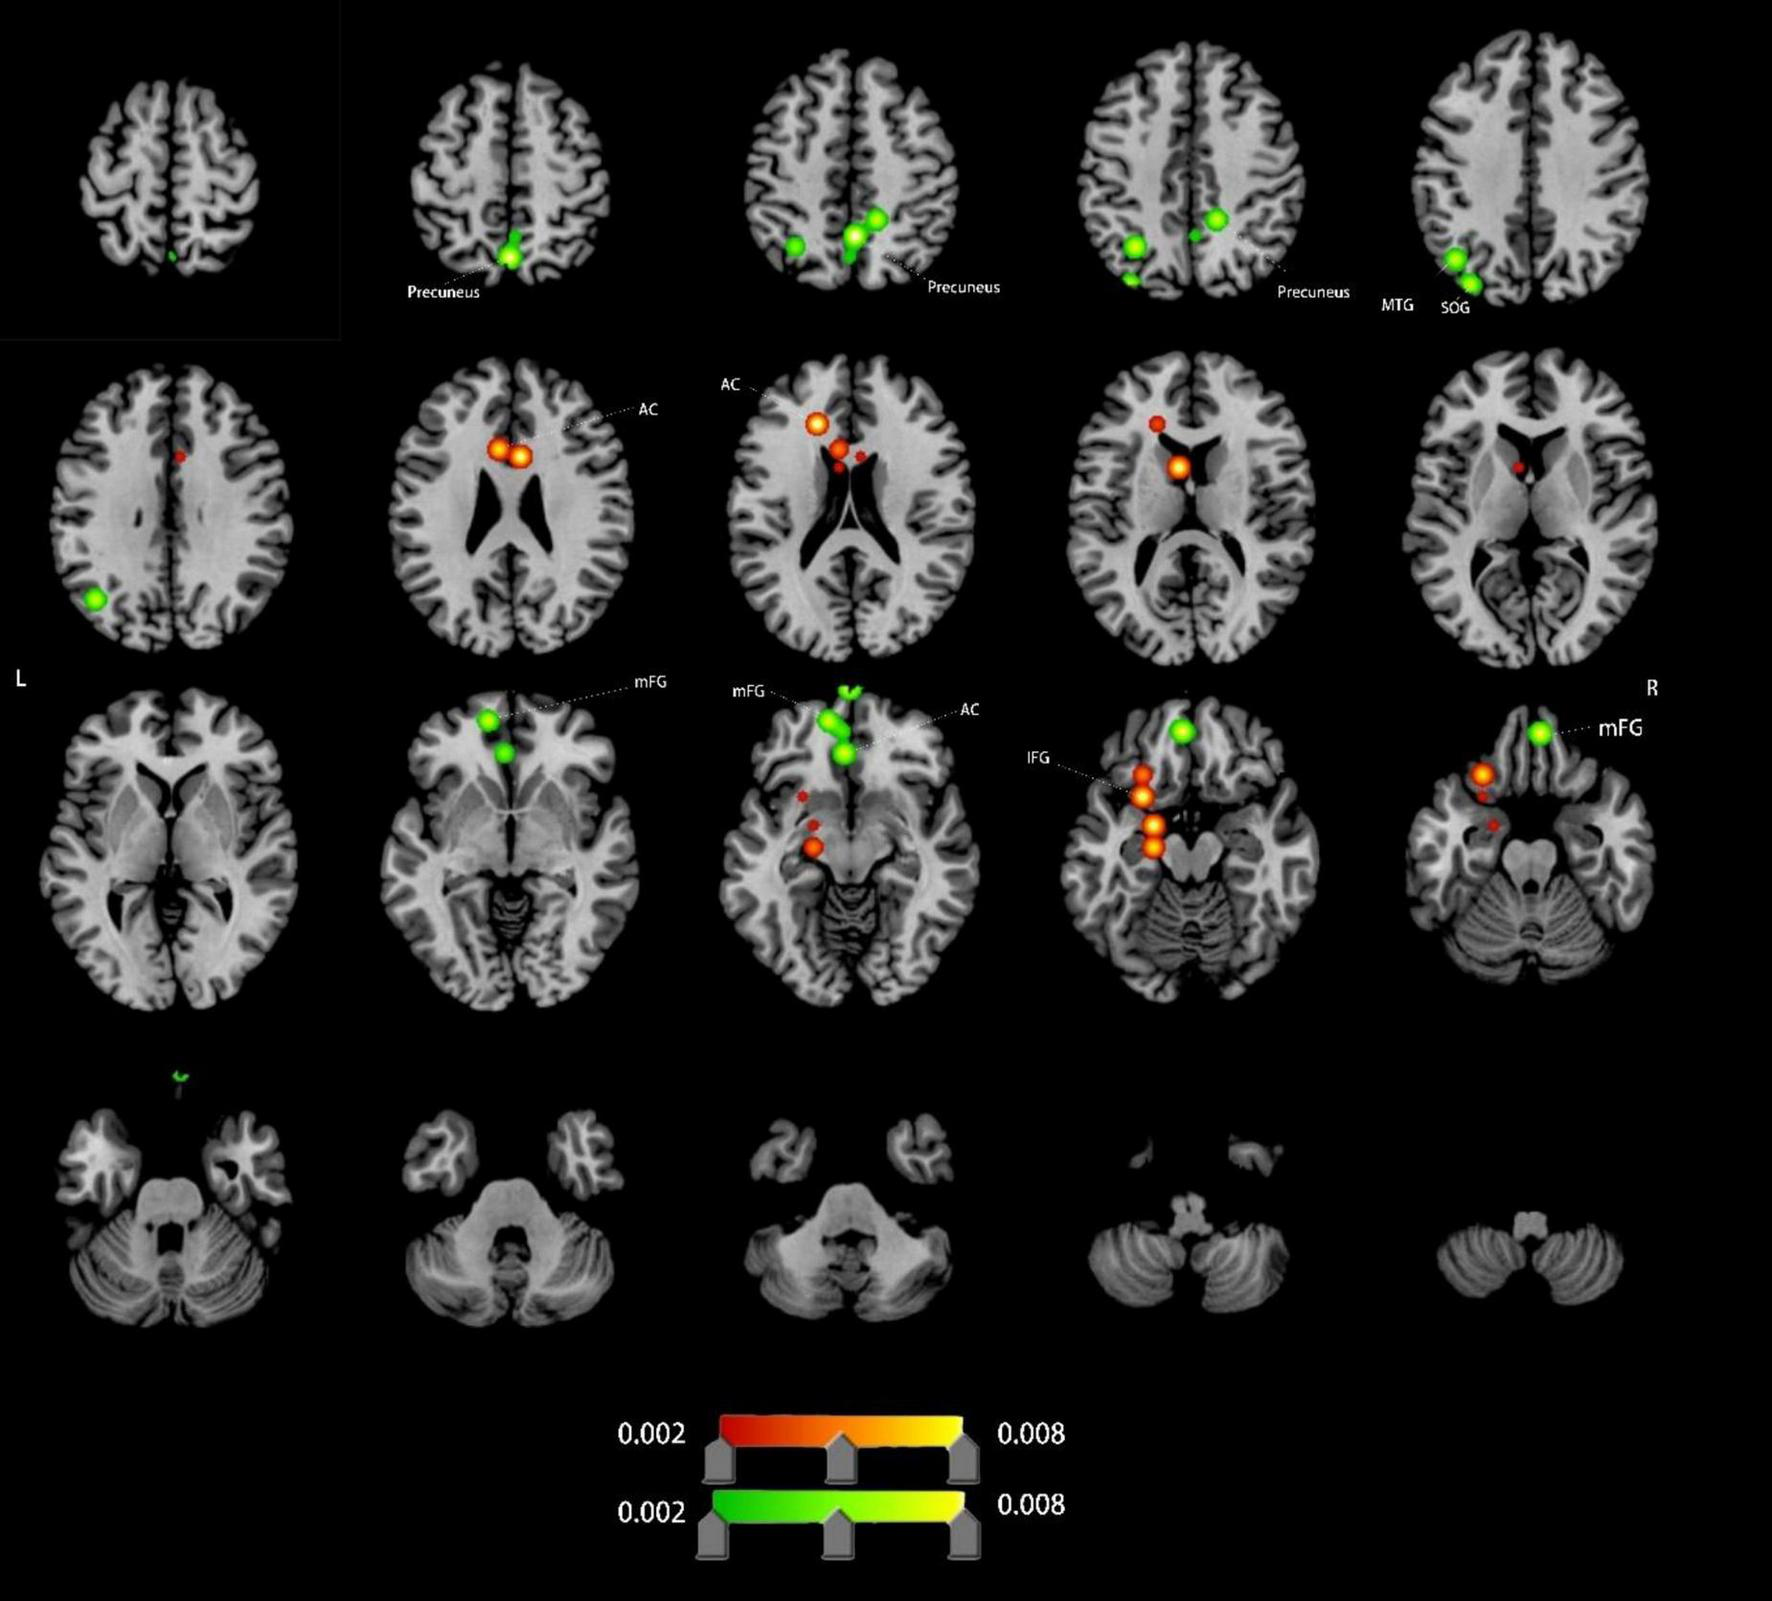

Altered ALFF in VCI patients

Compared to HCs, VCI patients demonstrated significant ALFF alterations, characterized by increased ALFF (4 clusters), left anterior cingulate cortex (ACC), left inferior frontal gyrus (IFG), decreased ALFF (11 clusters),left ACC (distinct subregion from increased cluster), bilateral medial frontal gyrus (mFG), bilateral precuneus, left middle temporal gyrus (MTG) and left superior occipital gyrus (SOG). Detailed spatial distributions and statistical thresholds are presented in Figure 2 and Table 1.

FIGURE 2

Brain regions showing increased/decreassed ALFF in VCI patients compared to HCs. Red indicates regions of increased ALFF values. Green indicates regions of decreased ALFF values. AC, anterior cingulate; IFG, inferior frontal gyrus; mFG, medial frontal gyrus; MTG, middle temporal gyrus; SOG, superior occipital gyrus.

ALFF Abnormalities: ALFF alterations were predominantly localized in prefrontal, precuneus, and temporal regions. Increased ALFF in the left AC and IFG suggests enhanced neuronal excitability, potentially reflecting compensatory mechanisms for cognitive control, emotional processing, and multitasking in response to cerebral ischemia (Briggs et al., 2019; Kolling et al., 2016; Monosov et al., 2020; Sato et al., 2023; Shinozaki et al., 2016; Shu et al., 2022). Conversely, decreased ALFF in mFG, bilateral precuneus, and other default mode network (DMN) hubs indicates resting-state dysfunction, likely contributing to episodic memory decline, executive dysfunction, and emotional dysregulation in VCI (Dadario and Sughrue, 2023; Frascarelli et al., 2015; Myung et al., 2016).